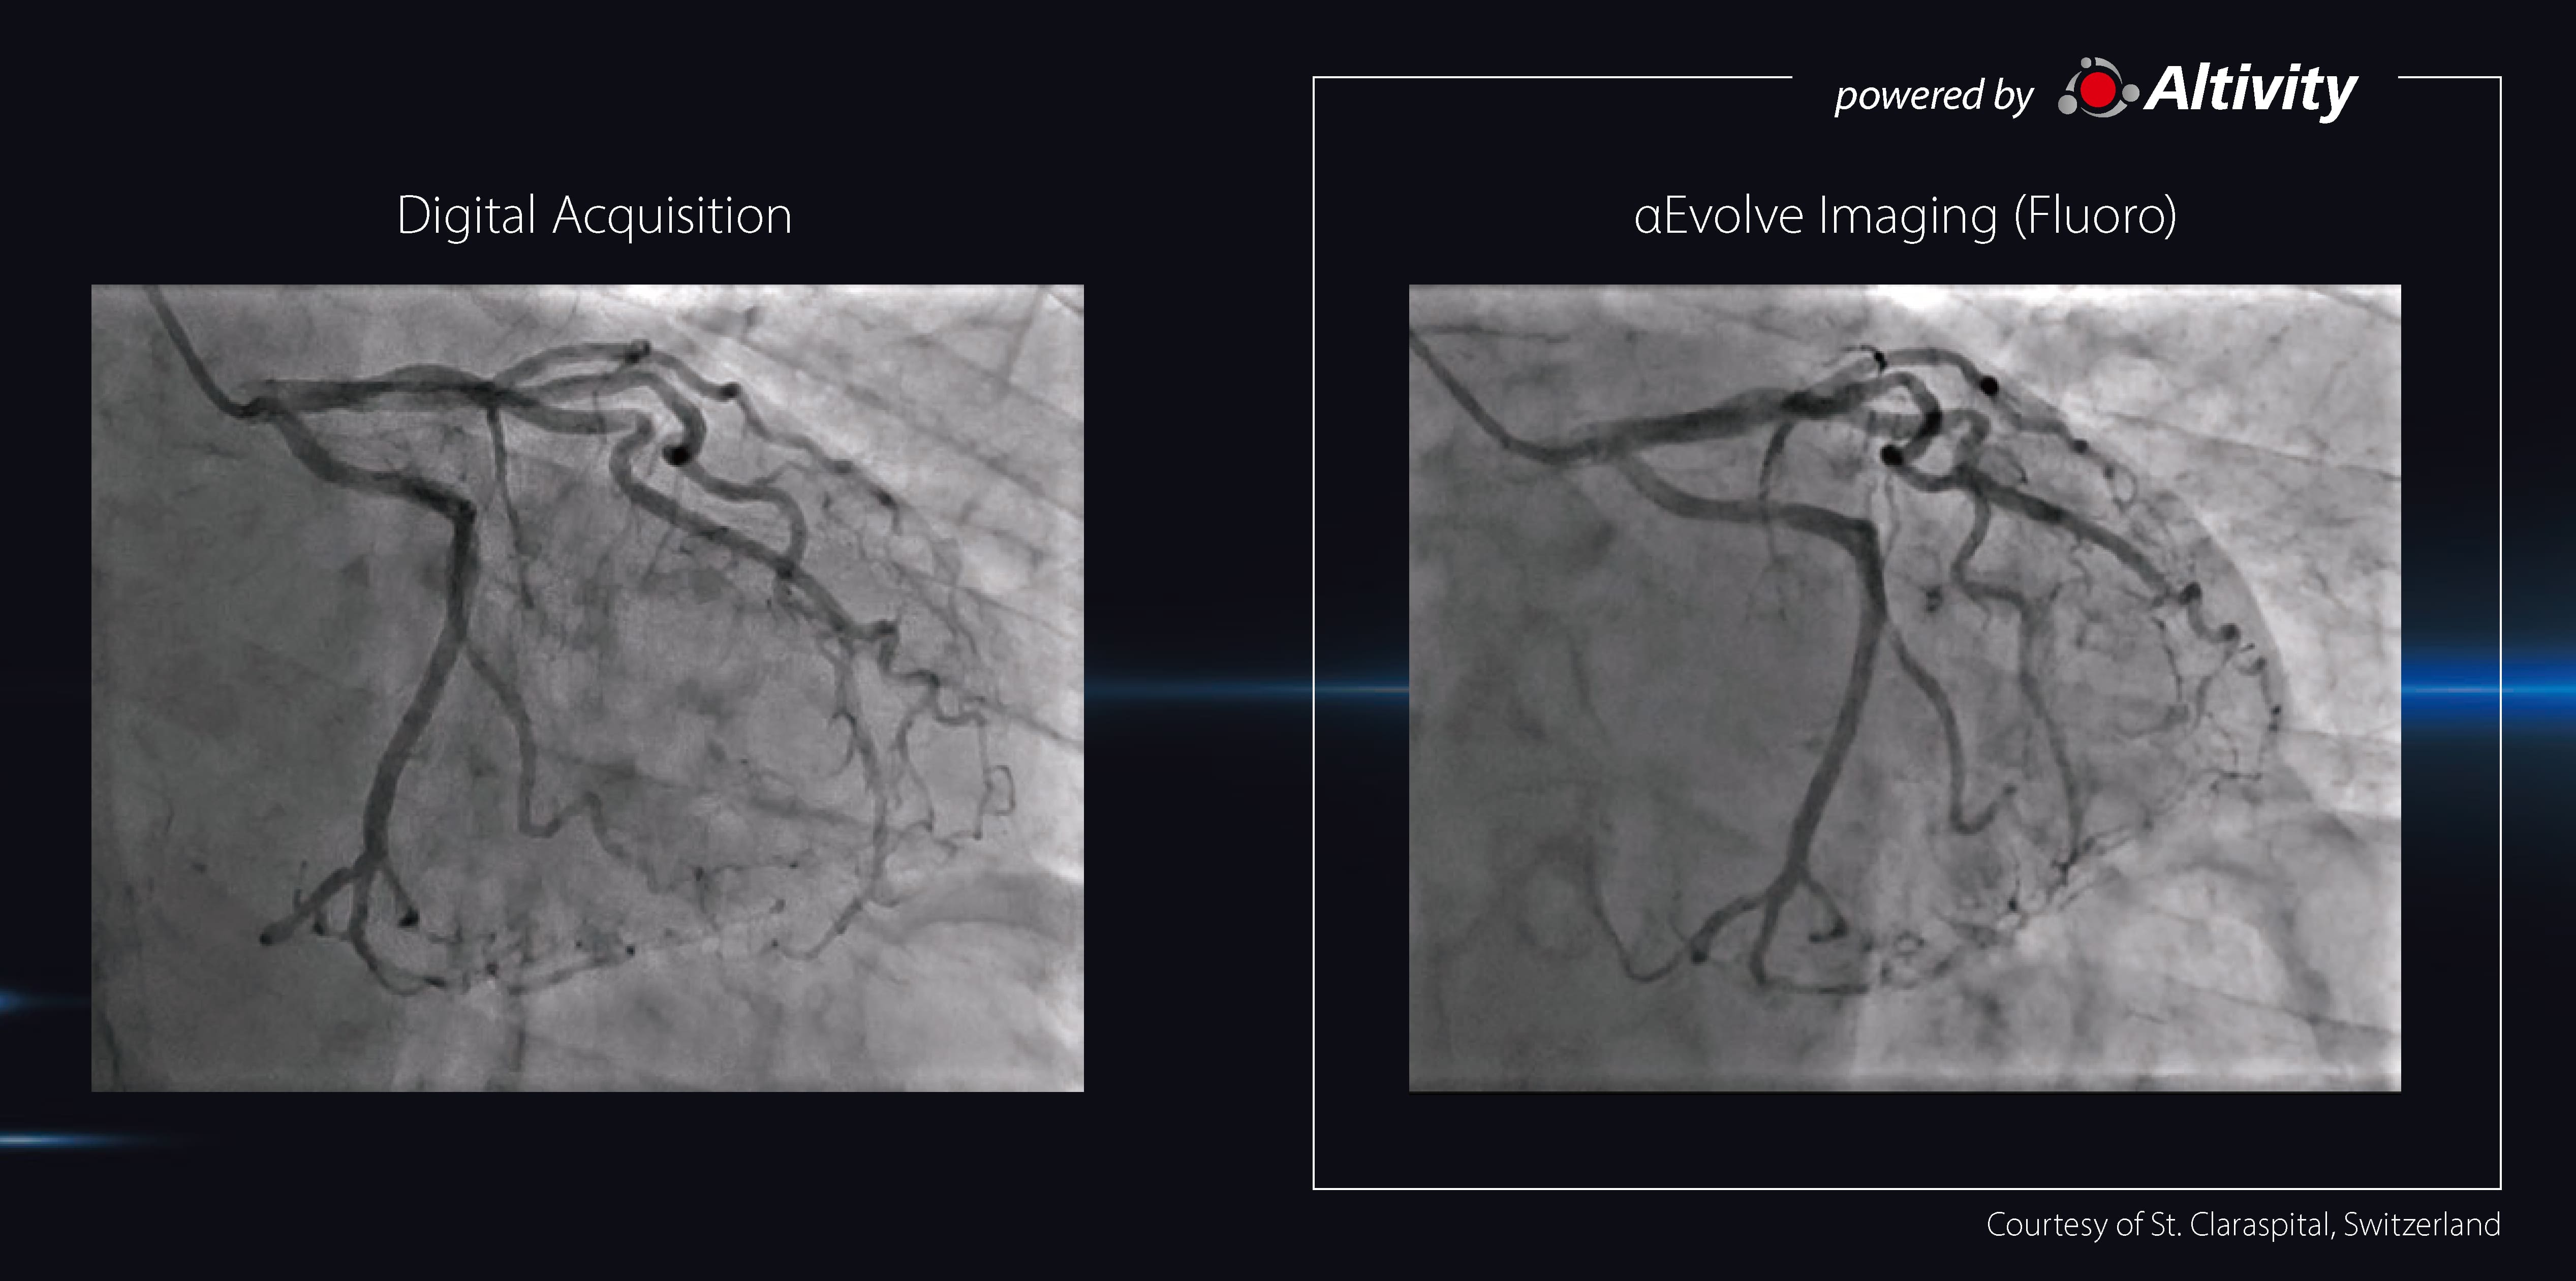

-Experience enhanced clarity with aEvolve Imaging, in real-time:

Clear fluoroscopic imaging enhances confidence and can help improve clinical outcomes and procedural efficiency. ฮฑEvolve Imaging achieves high-quality images through Deep Learning*1-based noise reduction and multi-frequency processing.

98% of physicians agree that ฮฑEvolve Imaging enhances the visibility of device compared to the conventional image processing.

-DA-equivalent image quality

96% of physicians agree that the ฮฑEvolve Imaging fluoro can achieve an image quality that can replace DA.*2